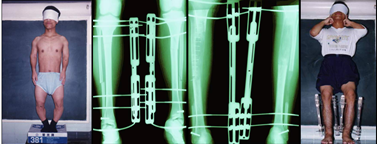

病例4:先天侏儒畸形,双胫骨仅17CM,身高128CM,伴“O”形腿。术后情况:纠正O型腿并延长14cm。